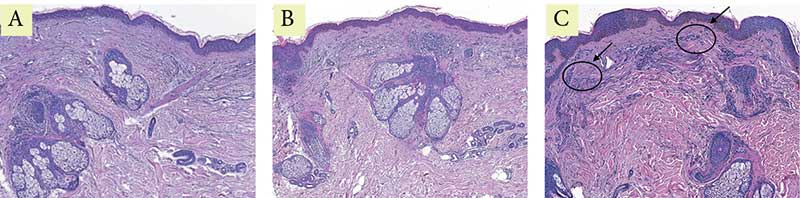

Рис. 1. Пациентка Л. Окраска гематоксилин-эозином: A – до процедуры; B – через месяц после процедуры; C – через пять месяцев после процедуры